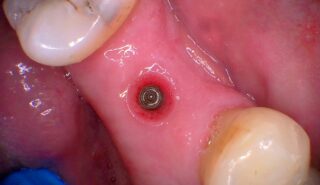

During the healing phase, a small healing cap is used to protect the implant and shape the surrounding gum tissue, preparing the area for the final crown or bridge.

After a problematic tooth is removed, the jawbone is left to heal and prepare for a dental implant. This step is essential for the long-term success of the treatment.